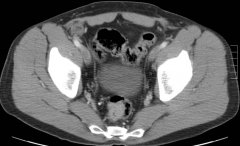

有很多描述用于盆腔脓肿引流的入路。 经腹 经腹引流的优越性在于操作者比较方便,病人在操作过程中可以处于比较舒适的体位,并且能够安全简易地进行皮肤固定。缺点在于操作不慎可能会对髂外或腹壁下血管造成损害,这是因为要避免刺破肠道,子宫或膀胱而必须...

有很多描述用于盆腔脓肿引流的入路。 经腹 经腹引流的优越性在于操作者比较方便,病人...